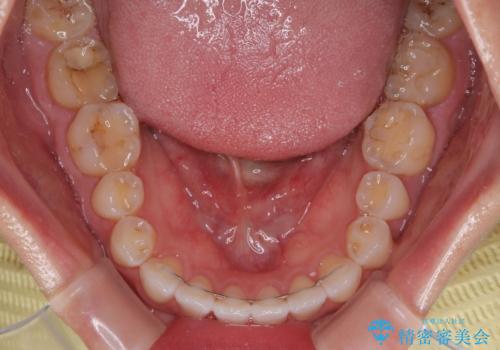

- 上下前歯のデコボコを気にして来院された患者様です。

ワイヤー矯正でもマウスピース矯正でも可能でしたが、短期間で、自身の手を煩わせることなく治療を行いたいとのことで、ワイヤー装置にて矯正治療を行うこととしました。